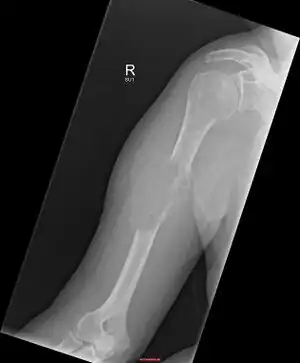

Solitary plasmacytoma in the long bone of the upper arm

Plasmacytoma, is most frequently a cancerous bone tumor made up of abnormal plasma cells, generally affecting the skull and central bones with localized pain and sometimes a broken bone.[1][2] When it grows outside bone in soft tissue, it is called an extramedullary plasmacytoma.[2] It is a solitary plasmacytoma when there is only one tumor, and multiple myeloma when there are many.[2]

Skeletal surveys are used to ensure there are no other primary tumors within the axial skeleton. MRI can be used to assess tumor status and may be advantageous in detecting primary tumors that are not detected by plain film radiography. PET-CT may also be beneficial in detecting extramedullary tumours in individuals diagnosed with SPB. CT imaging may be better than plain film radiography for assessing bone damage.[6][7]